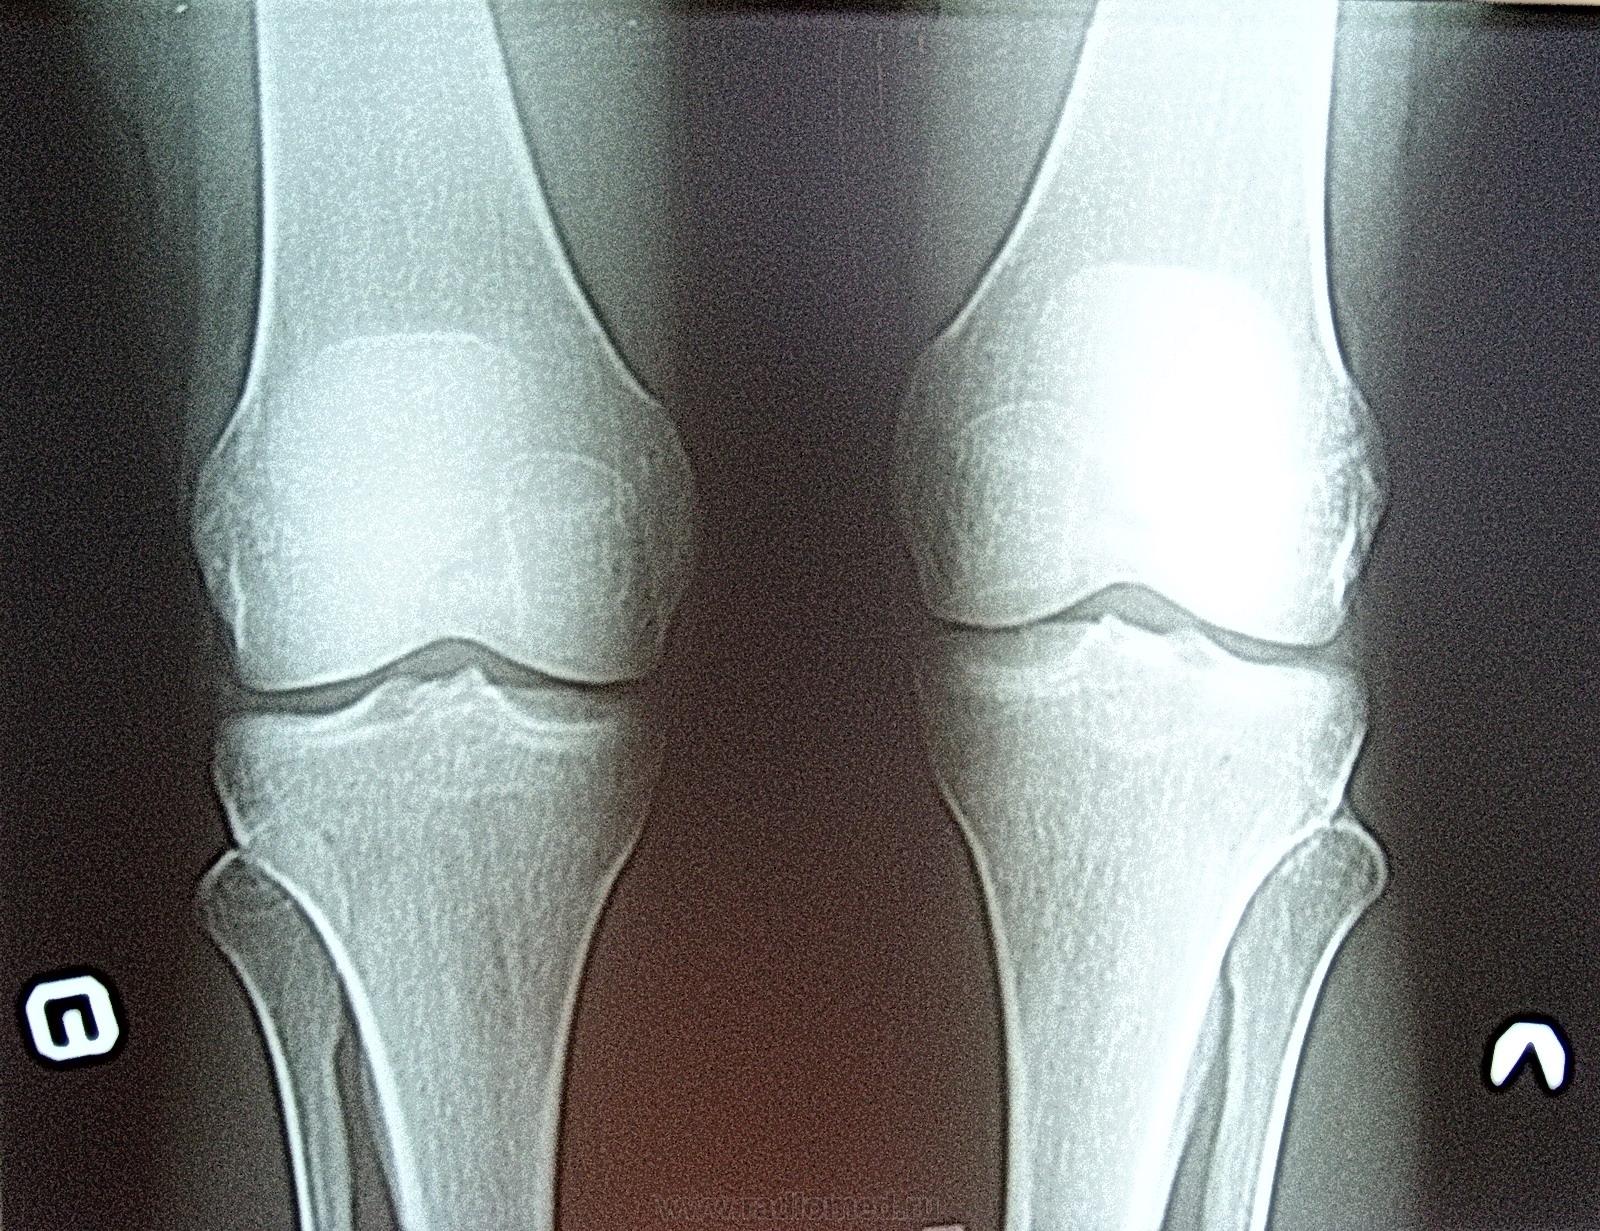

Молодая женщина 25 лет пришла самостоятельно на рентген коленных суставов, точнее правого. Левый - решила сделать "для кучи". Меня заинтересовала правая м\берцовая кость, точнее её метафизарный отдел, по сравнени. с левой. Со слов женщины боли сильные в правом коленном суставе. Травм не было. А какие ваши мнения уважаемые коллеги?

Очень плохое качетво выложенных Вами изображений (преимущественно прямого снимка) - никакой костной патологии не вижу.